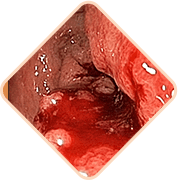

Sensación de pesadez o cuerpo extraño en el recto

Picazón y ardor en el área del ano

Dolor al defecar, caminar y sentarse

Sensibilidad de los ganglios hemorroidales al palpar

Sangrado durante los movimientos intestinales o con esfuerzo

3 peligros mortales de hemorroides si no se trata a tiempo

Cualquiera de los siguientes puede ser

la causa de la muerte súbita del paciente!

Las heces contienen una cantidad gigantesca de gérmenes, bacterias y hongos. Si la infección ingresa al tejido pélvico y a los órganos vecinos, es posibleuna inflamación peligrosa y una infección de la sangre

Los vasos llenos del bulto hemorroidal son muy débiles. A menudo se rompen. El grado de pérdida de sangre en este caso puede ser tal que sea necesario transfusión de sangre

Se forman coágulos de sangre en los vasos. Estos coágulos de sangre pueden desprenderse y obstruir los vasos de los órganos internos, interrumpir la circulación sanguínea y causar un bloqueo en las arterias pulmonares.La probabilidad de muerte es alta.